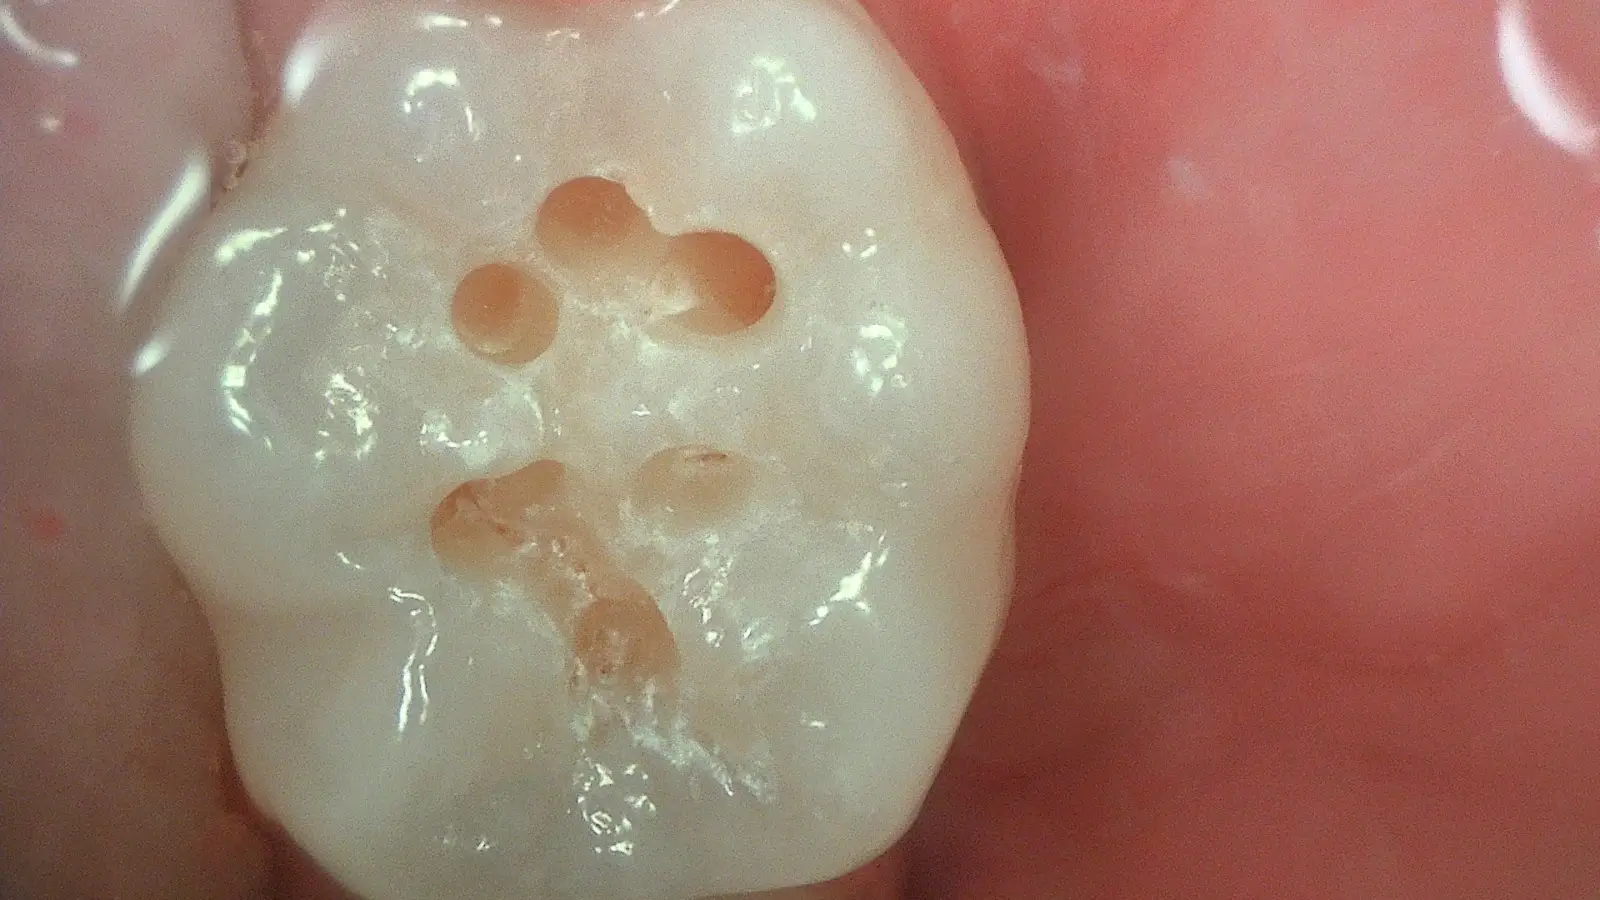

Early Caries & Plaque Detection

Patented Acteon fluorescence highlights early carious lesions and plaque as distinct colour changes — visible before they appear on X-ray or to the naked eye.

Experience the exceptional Full HD detail and fluorescence diagnostics in real patient cases — from early caries detection to minimally invasive restorations.